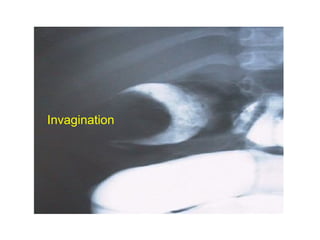

Invagination

• Cliché abdomen sans préparation

– Boudin d ’invagination : opacité allongée (50 à

60 %)

– Contenu aérique et fécal colique pauvre

– Disparition du granité cæcal, niveaux HA

• Échographie abdominale

– Examen diagnostic de référence

– boudin = coupe transversale: aspect de “cible”,

coupe longitudinale: aspect en “ pince de

crabes”

• Lavement opaque (baryte, iode, air)

= diagnostic et traitement